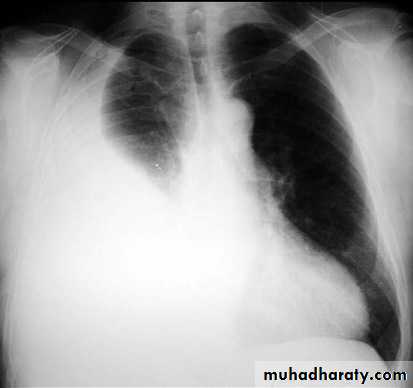

with large volume effusions, mediastinal shift occurs away from the effusion (note: if coexistent collapse dominates then mediastinal shift may occur towards the effusion)

Pneumothorax refers to the presence of gas (air) in the pleural space. When this collection of gas is constantly enlarging with resulting compression of mediastinal structures it can be life-threatening and is known as a tension pneumothoraxIt is useful to divide pneumo thoraces into three categories :

A pneumothorax is, when looked for, usually relatively easily appreciated. Typically they demonstrate:

visible visceral pleural edge see as a very thin, sharp white line

no lung markings are seen peripheral to this line

the peripheral space is radiolucent compared to adjacent lung

the lung may completely collapse

the mediastinum should not shift away from the pneumothorax unless a tension pneumothorax is present